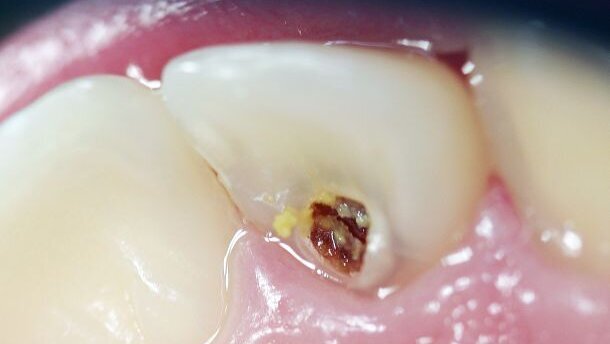

Toen ik net begon, zag je ontzettend veel diepe cariëslaesies en ook hele monden die waren aangedaan. Nu zie je dat zelden en vind je een diepe cariëslaesie hooguit in één of twee elementen. De rest van de mond is vaak gewoon gezond, wat ik in mijn beginperiode als tandarts echt nooit zag. Dan was er helemaal geen sprake van dat je ging restaureren, daar ging direct de tang op. Alles eruit, want er was geen redden meer aan. Nu moet je overwegen wat te doen, toen overwoog ik niet zoveel. Dat is dus flink veranderd.

Het is van belang dat je het element vitaal houdt en dus niet direct de pulpa in duikt. Daarbij is het essentieel om te differentiëren wat nog wel kan, en wat niet meer. Eigenlijk zijn er drie mogelijkheden. Als een element er zo slecht aan toe is dat je het niet meer kunt redden, ga je over tot extractie. Als een element in betrekkelijk slechte staat is, kun je het vaak met een endodontische behandeling nog redden. De derde mogelijkheid is dat het er slecht uitziet, maar dat je met wat voorzichtig manipuleren het element kunt herstellen. Hoe meer kennis en ervaring je hebt met diepe cariëslaesies, hoe makkelijker het wordt om een goede keuze te maken. Er zitten natuurlijk overgangsgebieden tussen de drie opties, dus hoe meer laesies je ziet, hoe gemakkelijker je kunt herkennen of een element vitaal te houden is.

Een diepe cariëslaesie is niet te missen. De kunst is het herkennen van de voorstadia, zodat je kunt voorkomen dat een laesie zich verder ontwikkelt. Daarvoor is het belangrijk dat je patiënten regelmatig ziet. Dat geldt vooral voor de risicogroepen, zoals kinderen en ouderen. In de leeftijd daartussen, (jong)volwassenen, zie je diepe cariëslaesies vele malen minder. Als je dan cariëslaesies tegenkomt, is het vaak een bewuste keuze om het gebit niet te verzorgen: mensen die het niets kan schelen. Vaak zijn dit verslaafden, zeker op de jongvolwassen leeftijd. Bij hen heb ik flinke cariësexplosies gezien, of jarenlang verslaafden bij wie het hele gebit uit de mond is gerot. Maar onder ‘normale’ omstandigheden zie je op die leeftijd geen diepe cariëslaesies.

Ik denk dat de trend van de afgelopen veertig jaar doorzet en we steeds minder en minder diepe cariëslaesies gaan zien. Al zal er altijd een groep mensen blijven bij wie het blijft voorkomen, omdat zij hun gebit verwaarlozen. Ik verwacht niet nog eens zo’n doorbraak als de fluoridetandpasta, iets wat zoveel effect zal hebben op de incidentie van diepe cariëslaesies. Al is er wel wetenschappelijke kennis over cariës die nog onvoldoende wordt toegepast in de praktijk. Zo weten we inmiddels dat je cariës kunt stoppen door niet alles te verwijderen en de laesie netjes af te sluiten. Toch heerst bij veel collega’s nog het idee dat cariës altijd volledig weggehaald moet worden. Doe je dat niet, dan ben je een slechte tandarts. Niets is minder waar, het is nergens voor nodig om alle cariës weg te boren. Op een gegeven moment moet je die wetenschap accepteren en ernaar gaan behandelen. Als het veld meegaat in dit soort wetenschappelijke ontwikkelingen, denk ik dat diepe cariëslaesies bijna volledig uit onze praktijk zullen verdwijnen.